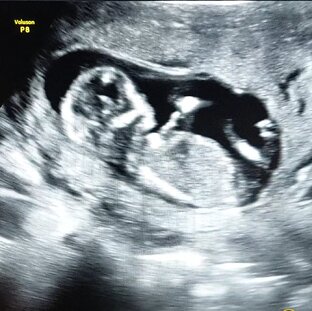

Все мои бзики, загоны и немного медицинской информации.

подборка · 26 материалов